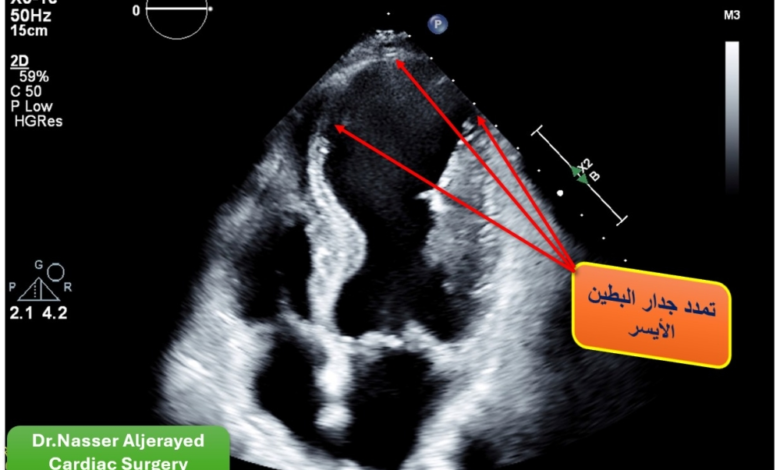

تُعد الجلطات القلبية الشديدة من أخطر الحالات الطبية الطارئة، وفي بعض الحالات النادرة، تؤدي هذه الجلطات إلى مضاعفات كارثية مثل تمزق عضلة القلب. وقد كشف الفريق الطبي المعالج أن الجلطة الشديدة التي تعرض لها المريض السبعيني أدت إلى تمزق بالغ في عضلة الحاجز بين البطينين الأيمن والأيسر، مما أسفر عن حدوث ثقب كبير بمقاس «2.5 × 2.5» سنتيمتر مربع. هذا النوع من التمزق يُصنف طبياً وعالمياً كأحد أخطر المضاعفات التي تتطلب تدخلاً جراحياً عاجلاً ودقيقاً للغاية، حيث ترتفع نسب الوفيات في مثل هذه الحالات بشكل كبير إذا لم يتم التدخل الجراحي في الوقت المناسب لإنقاذ المريض.

أسهم التدخل الجراحي الدقيق، والذي يُنفذ للمرة الأولى في المدينة ممثلة بمركز صحة القلب، في إنهاء معاناة المريض من احتشاء وتمدد خطير في عضلة البطين الأيسر. وقد أوضح الكادر الطبي أن العملية الجراحية تكللت بالنجاح التام بفضل الله ثم بكفاءة الفريق الطبي وتوفر أحدث التقنيات. وأظهر المريض استجابة إيجابية وسريعة للعلاج، مما مكنه من التعافي في وقت قياسي. وقد غادر المريض السبعيني أروقة المستشفى وهو يتمتع بصحة جيدة بعد ستة أيام فقط من إجراء هذا التدخل الطبي الدقيق، مما يؤكد على جودة الرعاية الصحية الفائقة التي تلقاها.